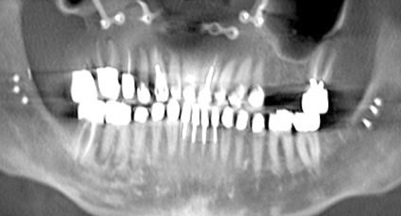

The Toronto Conference in 1982, chaired by Professor George Zarb and presented by Professor Per-Ingvar Brånemark, was a seminal event that changed edentulous treatment planning concepts irrevocably. No longer was it necessary to rebuild lost bone through grafting alone in either arch. The severely atrophic mandible, for example, could be treated with as few as four implants used to support a bone-sparing prosthesis through integrated tooth analogs, as demonstrated in Figure 1 through Figure 3. Here, an 81-year-old patient presented with severe mandibular atrophy (Figure 1) from denture wear since a very young age and had a history of being unable to manage a mandibular prosthesis despite numerous attempts at new denture construction. Four vertical machined-surface osseointegrated implants were placed in 1983 by Professor Brånemark, and all four penetrated the inferior cortex up to 3 mm to 4 mm in depth, as shown on the immediate postoperative panoramic film (Figure 2). At 4 years and 5 months, reparative bone had formed to the apices of all implants (Figure 3), and all of them remained in uncompromised function until the patient passed away at age 90.

Fig 1. 81-year-old patient had severe mandibular atrophy from many years of denture wear and had a history of inability to manage a mandibular prosthesis.

Figure 1

Fig 2. Four vertical machined-surface osseointegrated implants placed in 1983 penetrated the inferior cortex up to 3 mm to 4 mm in depth, immediate postoperative.

Figure 2

Fig 3. At 4 years and 5 months follow-up, reparative bone had formed to the apices of all implants.

Figure 3